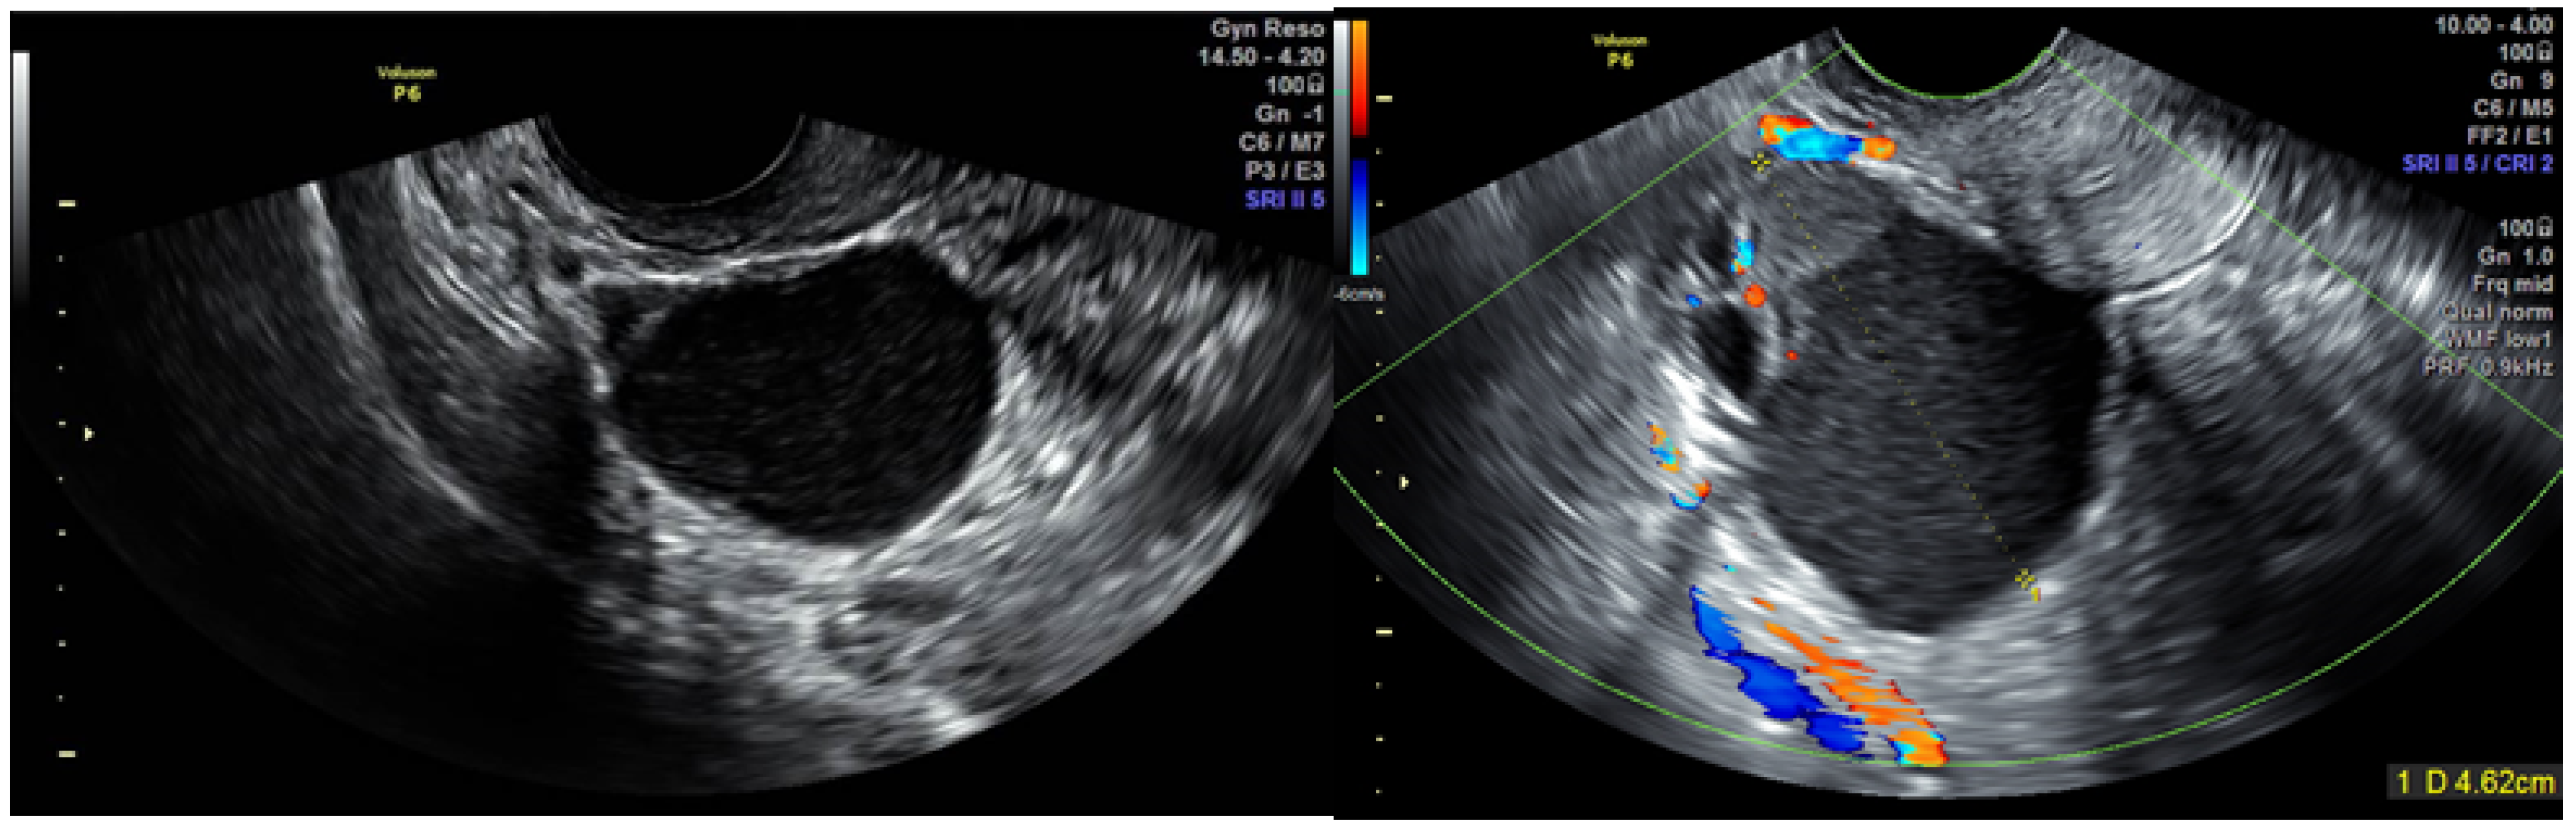

2.2. TVUS Evaluation of Adnexal Masses

- Van Holsbeke, C.; Van Calster, B.; Guerriero, S.; Savelli, L.; Paladini, D.; Lissoni, A.A.; Czekierdowski, A.; Fischerova, D.; Zhang, J.; Mestdagh, G.; et al. Endometriomas: Their ultrasound characteristics. Ultrasound Obstet. Gynecol. 2010, 35, 730–740. [Google Scholar] [CrossRef]

- Testa, A.C.; Van Holsbeke, C.; Zannoni, G.F.; Fransis, S.; Moerman, P.; Vellone, V.G.; Mascilini, F.; Licameli, A.; Ludovisi, M.; Di Legge, A.; et al. Ovarian cancer arising in endometrioid cysts: Ultrasound findings. Ultrasound Obstet. Gynecol. 2011, 38, 99–106. [Google Scholar] [CrossRef] [PubMed]